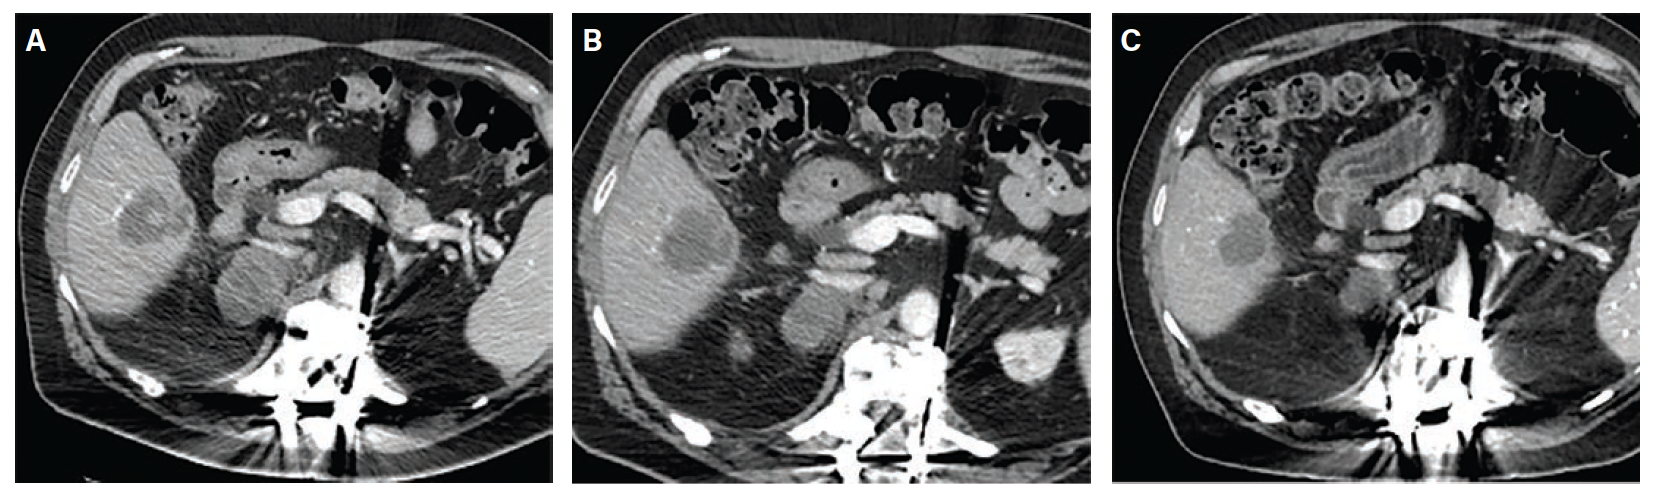

Index Procedure: The subject underwent TAE with Embrace HES under monitored anesthesia care (MAC). Left transradial access was obtained. A coaxial microcatheter system with a 1.7F 162-cm microcatheter (Instylla) inserted in a 2.8F 150-cm microcatheter (Progreat®, Terumo Medical Corporation) was used to embolize a single 3-mm feeder vessel with 1.6 mL of the Embrace (Figure 1). There was no clinical evidence of non-target embolization. Follow-Up: Repeat computed tomography performed at 30- and 90-days post index procedure indicated no evidence of revascularization and no local tumor progression (Figure 2). An independent Core Lab assessed a complete response in accordance with mRECIST criteria at both timepoints.

Index Procedure: The subject underwent TAE with Embrace HES under MAC for the new metastatic lesion. Left transradial access was obtained. A coaxial microcatheter system with a 1.7F 162-cm microcatheter (Instylla) inserted in a 2.8F 150-cm microcatheter (Progreat) was used to embolize 3 separate feeder vessels measuring 1.5 mm, 1 mm, and 1.3 mm with a total of 1.9 mL of the Embrace (Figure 3). All 3 vessels were embolized using the same microcatheter system. There was no clinical evidence of non-target embolization. Follow-Up: Repeat magnetic resonance imaging performed at 30- and 90-days post index procedure indicated no evidence of revascularization and no local tumor progression (Figure 4). An independent Core Lab assessed stable disease with a ~28% decrease in tumor diameter at 30 days and partial response with a ~45% decrease in tumor diameter at 90 days in accordance with RECIST 1.1 criteria.